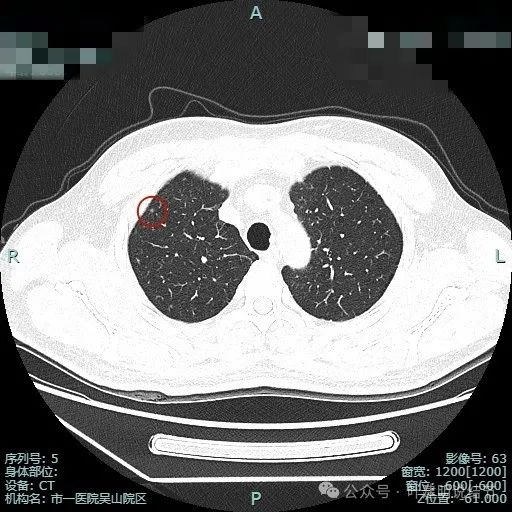

病灶5:右上叶前段血管旁微小磨玻璃结节,轮廓较清,与血管挨得近,考虑是肺泡上皮增生或不典型增生可能性大。

病灶6:右上叶后段磨玻璃结节,有浅分叶征,结合前面图上有血管穿行,考虑是肿瘤范畴的,以微浸润性腺癌或浸润性腺癌贴壁为主型可能性大。

病灶10:右上叶胸膜下微小结节,表面不平,密度也非实性,显得形态不太规则,考虑良性或肿瘤范畴的原位癌或微浸润性腺癌均可能,但太小了,如果只有此灶只需随访。

病灶11:右肺实性结节,边缘略模糊,缺乏膨胀感,考虑良性可能性大些。

病灶12:右下叶微小结节,点状,密度较高,良性增殖灶可能性大。